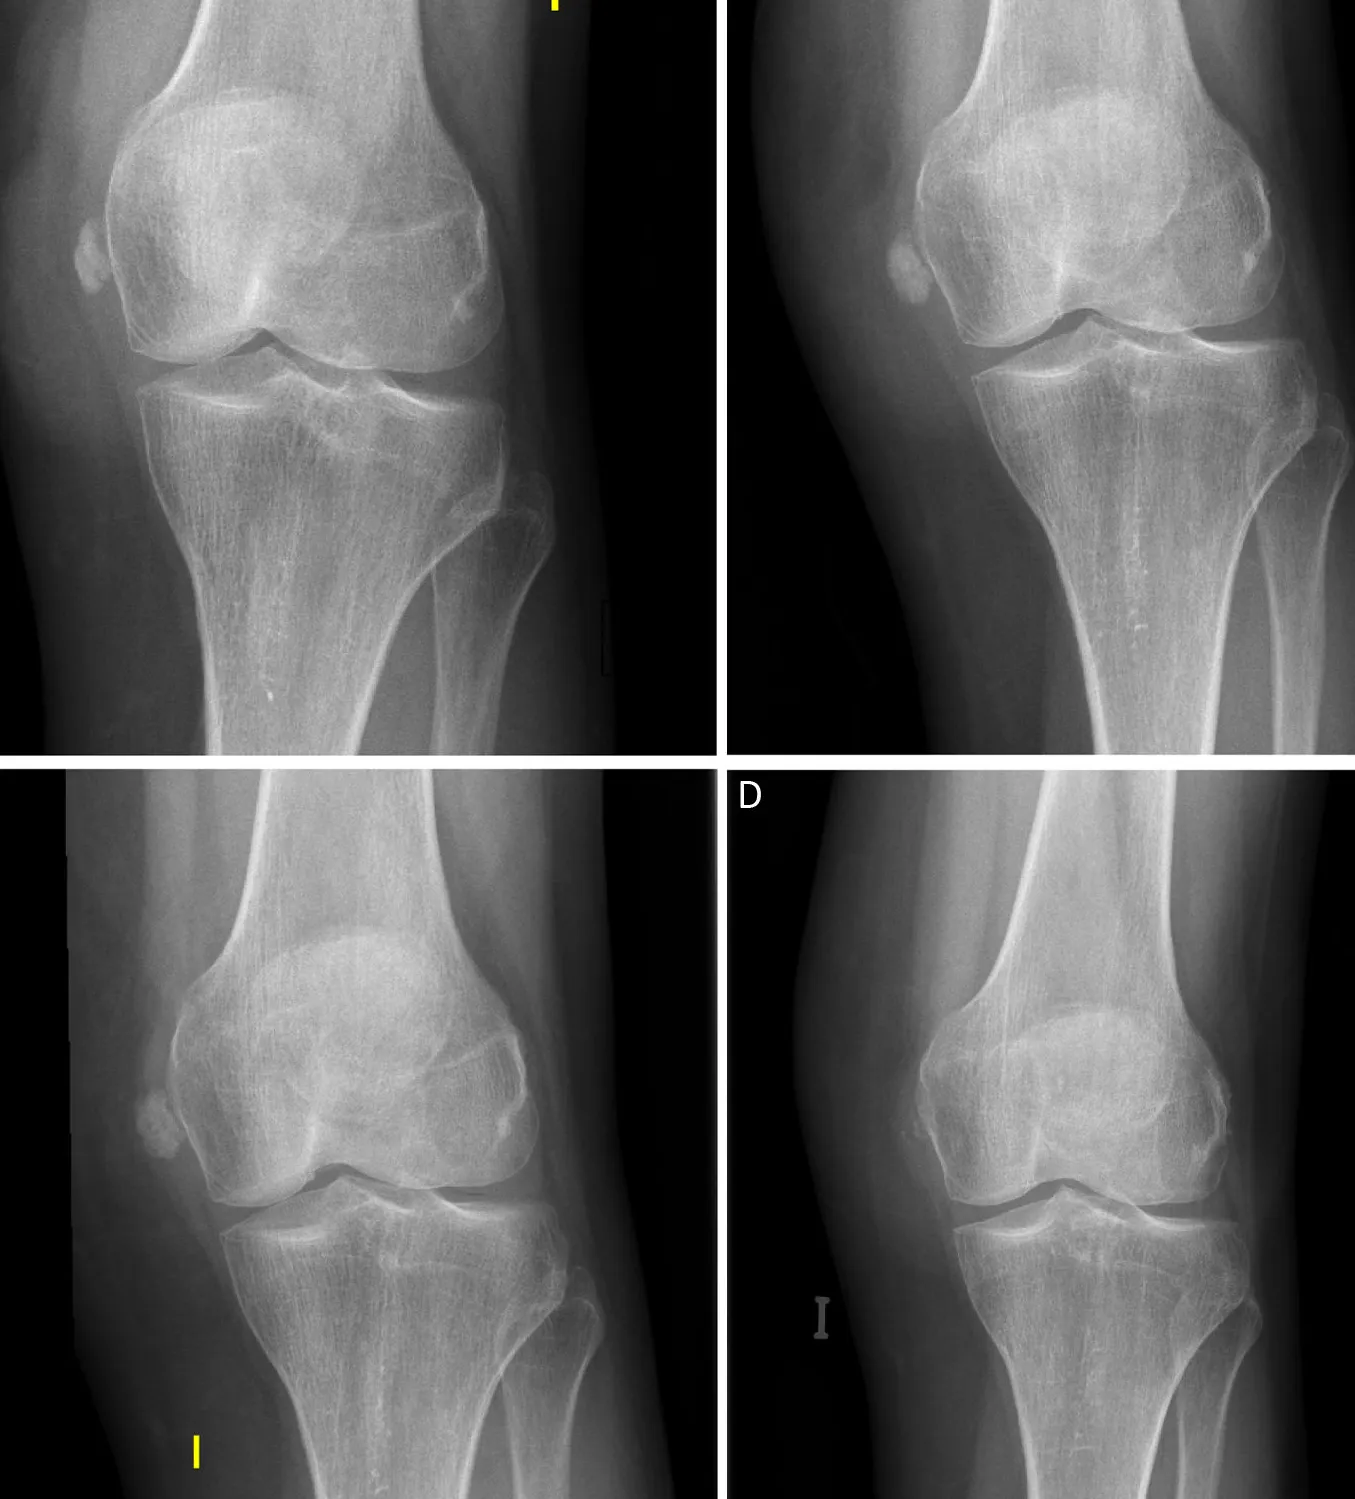

Una calcificación en la rodilla es el depósito de sales de calcio en los tendones o, más raramente, en otras estructuras como el menisco.

No es un "hueso extra", sino una respuesta del cuerpo a una agresión o sobrecarga crónica.

Resumen Visual de Calcificación rodilla